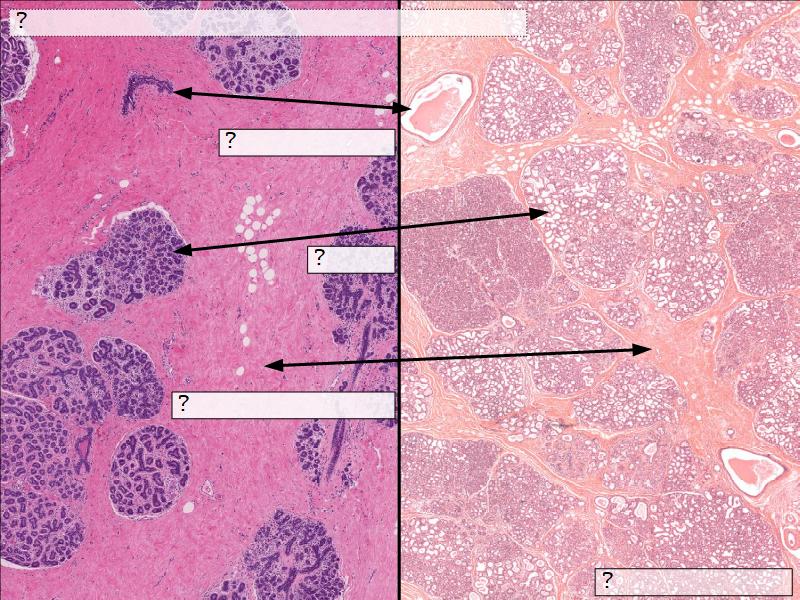

Two stages

- Resting

- Active

Resting and active

Describe the resting mammary gland and compare with the active gland.

(8)

Resting gland

- Connective tissue dominate

- More adipose tissue

- Glandular tissue reduced

Active gland

- Terminal ducts expand

- Forms alveoli

- Connective tissue reduced

- Adipose tissue reduced

- Glandular tissue dominate

Active gland

- Much larger than resting phase

- Terminal ducts proliferate to form alveoli

- Alveoli

- Surrounded by incomplete myoepithelial cells

Alveolar cells

- Apocrine secretion

- Active state

- Resting state